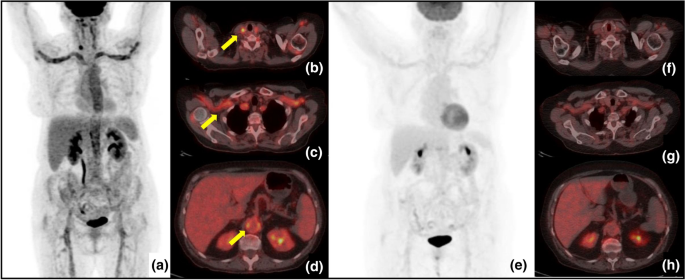

18F-Fluorodeoxyglucose positron emission tomography/computed tomography (FDG-PET/CT) is being used with increasing frequency due to its high sensitivity and the ability to detect the sites, extent, and severity of vessel inflammation. Within our cohort, this angiographic tool was employed in 12 patients (27.9%) at diagnosis and provided clear images of high sensitivity (Fig. 5). However, the limitations of FDG-PET/CT include a rapid decrease in sensitivity in patients treated with GC for 1–2 weeks prior to the examination, high-level radiation exposure, and the possible misinterpretation of the lesions as atherosclerosis [33, 34].

Fig. 5

figure 5

18F-FDG PET/CT in a 42-year-old female patient with type V Takayasu arteritis who complained of fatigue, weight loss, fever, and severe headache. Maximum intensity projection (MIP) (a) and axial fused images showed increased 18F-FDG uptake (yellow arrows) in the aorta and its main branches, particularly in carotid (b) and subclavian (c) arteries and in the distal abdominal aortic wall (d). After 6 months of therapy, follow-up PET/CT images show clearly decreased uptake in the large arteries (E–H)